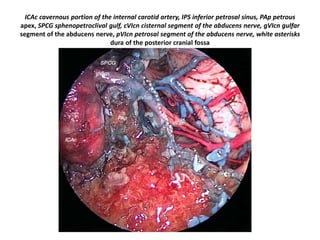

ICAc cavernous portion of the internal carotid artery, IPS inferior petrosal sinus, PAp petrous

apex, SPCG sphenopetroclival gulf, cVIcn cisternal segment of the abducens nerve, gVIcn gulfar

segment of the abducens nerve, pVIcn petrosal segment of the abducens nerve, white asterisks

dura of the posterior cranial fossa

Gulfar segment of 6th nerve (GS in left picture ) ( gVIcn in right picture ) - The

gulfar segment can be identified at the intersection of the sellar floor and the

ICAc cavernous portion of the internal carotid artery, IPS inferior petrosal sinus, PAp petrous apex, SPCG sphenopetroclival gulf, cVIcn cisternal segment of the

abducens nerve, gVIcn gulfar segment of the abducens nerve, pVIcn petrosal segment of the abducens nerve, white asterisks dura of the posterior cranial fossa –

The gulfar segment can be identified at the intersection of the sellar floor and the proximal parasellar internal carotid artery (ICA) (Barges-Coll et

al. 2010 ).

1. 6th N. crossing carotid at Petro-clival junction when viewing in lateral skull base

2. The gulfar segment can be identified at the intersection of the sellar floor and the

proximal parasellar internal carotid artery (ICA) (Barges-Coll et al. 2010 ).